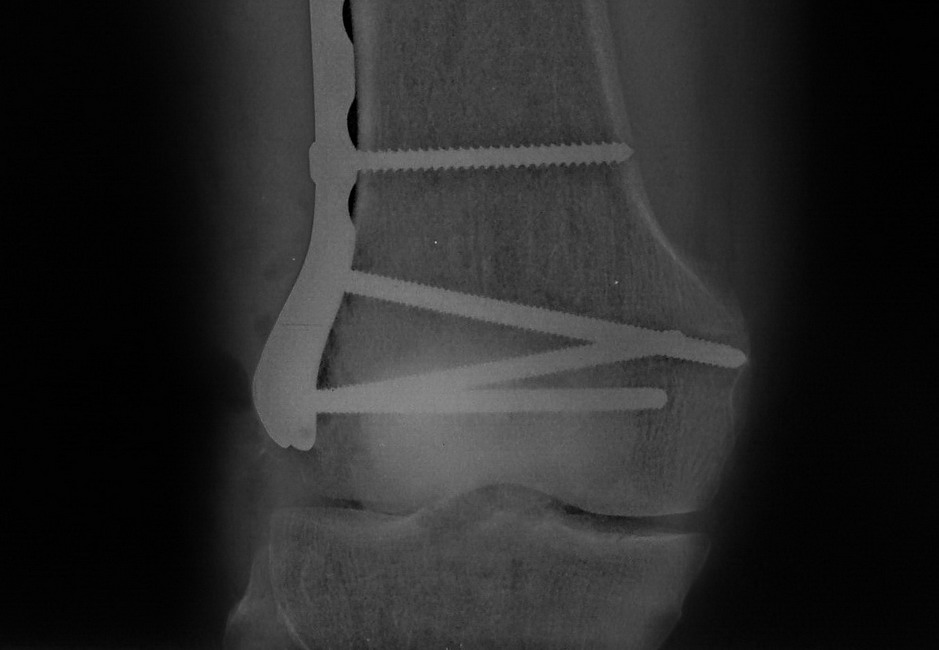

Остеосинтез LCP пластиной

В данном случае предпочтителен парапателлярный доступ, где необходимо создать лучший обзор к мыщелку. После остеотомии и репозиции фиксацию надо проделать поперечными винтами и дополнительно задней antiglade plate - сделанной из 1/3 tubular plate.

Здесь представлены различные варианты фиксации перелома, а также снимки комбинации перелома с повреждением хряща (12-19). Пластика хряща OsseoFit и установка custom made plate.